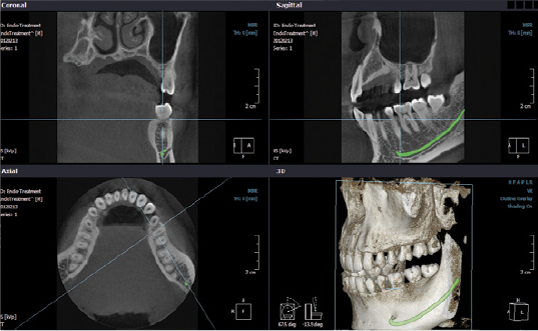

- Pianificazione terapeutica mediante trattamenti implantari

- Programmazione di chirurgia implatare guidata

- Follow up di trattamenti implantari

- Individuazione di fistole, sinusite mascellare odontogena e processi infiammatori periradicolari